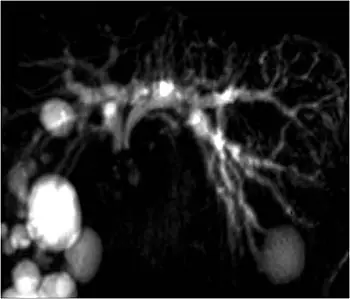

COLANGIOPANCREATOGRAFÍA POR RESONANCIA MAGNÉTICA (MRCP, POR SUS SIGLAS EN INGLÉS)

La colangiopancreatografía por resonancia magnética (MRCP, por sus siglas en inglés) es un tipo especial de resonancia magnética. Usa un programa de computadora que toma imágenes específicamente de los conductos biliar y pancreático, lugares en los que a menudo se encuentran los tumores. El líquido presente en forma natural en los conductos sirve como medio de contraste. La MRCP produce imágenes similares a una colangiopancreatografía retrógrada endoscópica (ERCP, por sus siglas en inglés) y es una excelente herramienta para visualizar los bloqueos en los conductos y los quistes pancreáticos.

La MRCP proporciona imágenes similares a una ERCP, pero sin los riesgos de un procedimiento de ERCP agresivo. La MRCP se puede usar en lugar de la ERCP con fines de diagnóstico si no se requieren intervenciones terapéuticas, como la colocación de una endoprótesis para aliviar la ictericia.

La MRCP se puede usar para diagnosticar una causa alternativa de la ictericia o una función hepática elevada, como los cálculos del conducto biliar, los tumores en el intestino delgado cerca de la abertura de los conductos biliar y pancreático o un tipo de tumor llamado neoplasia papilar mucinoso intraductal (IPMN).